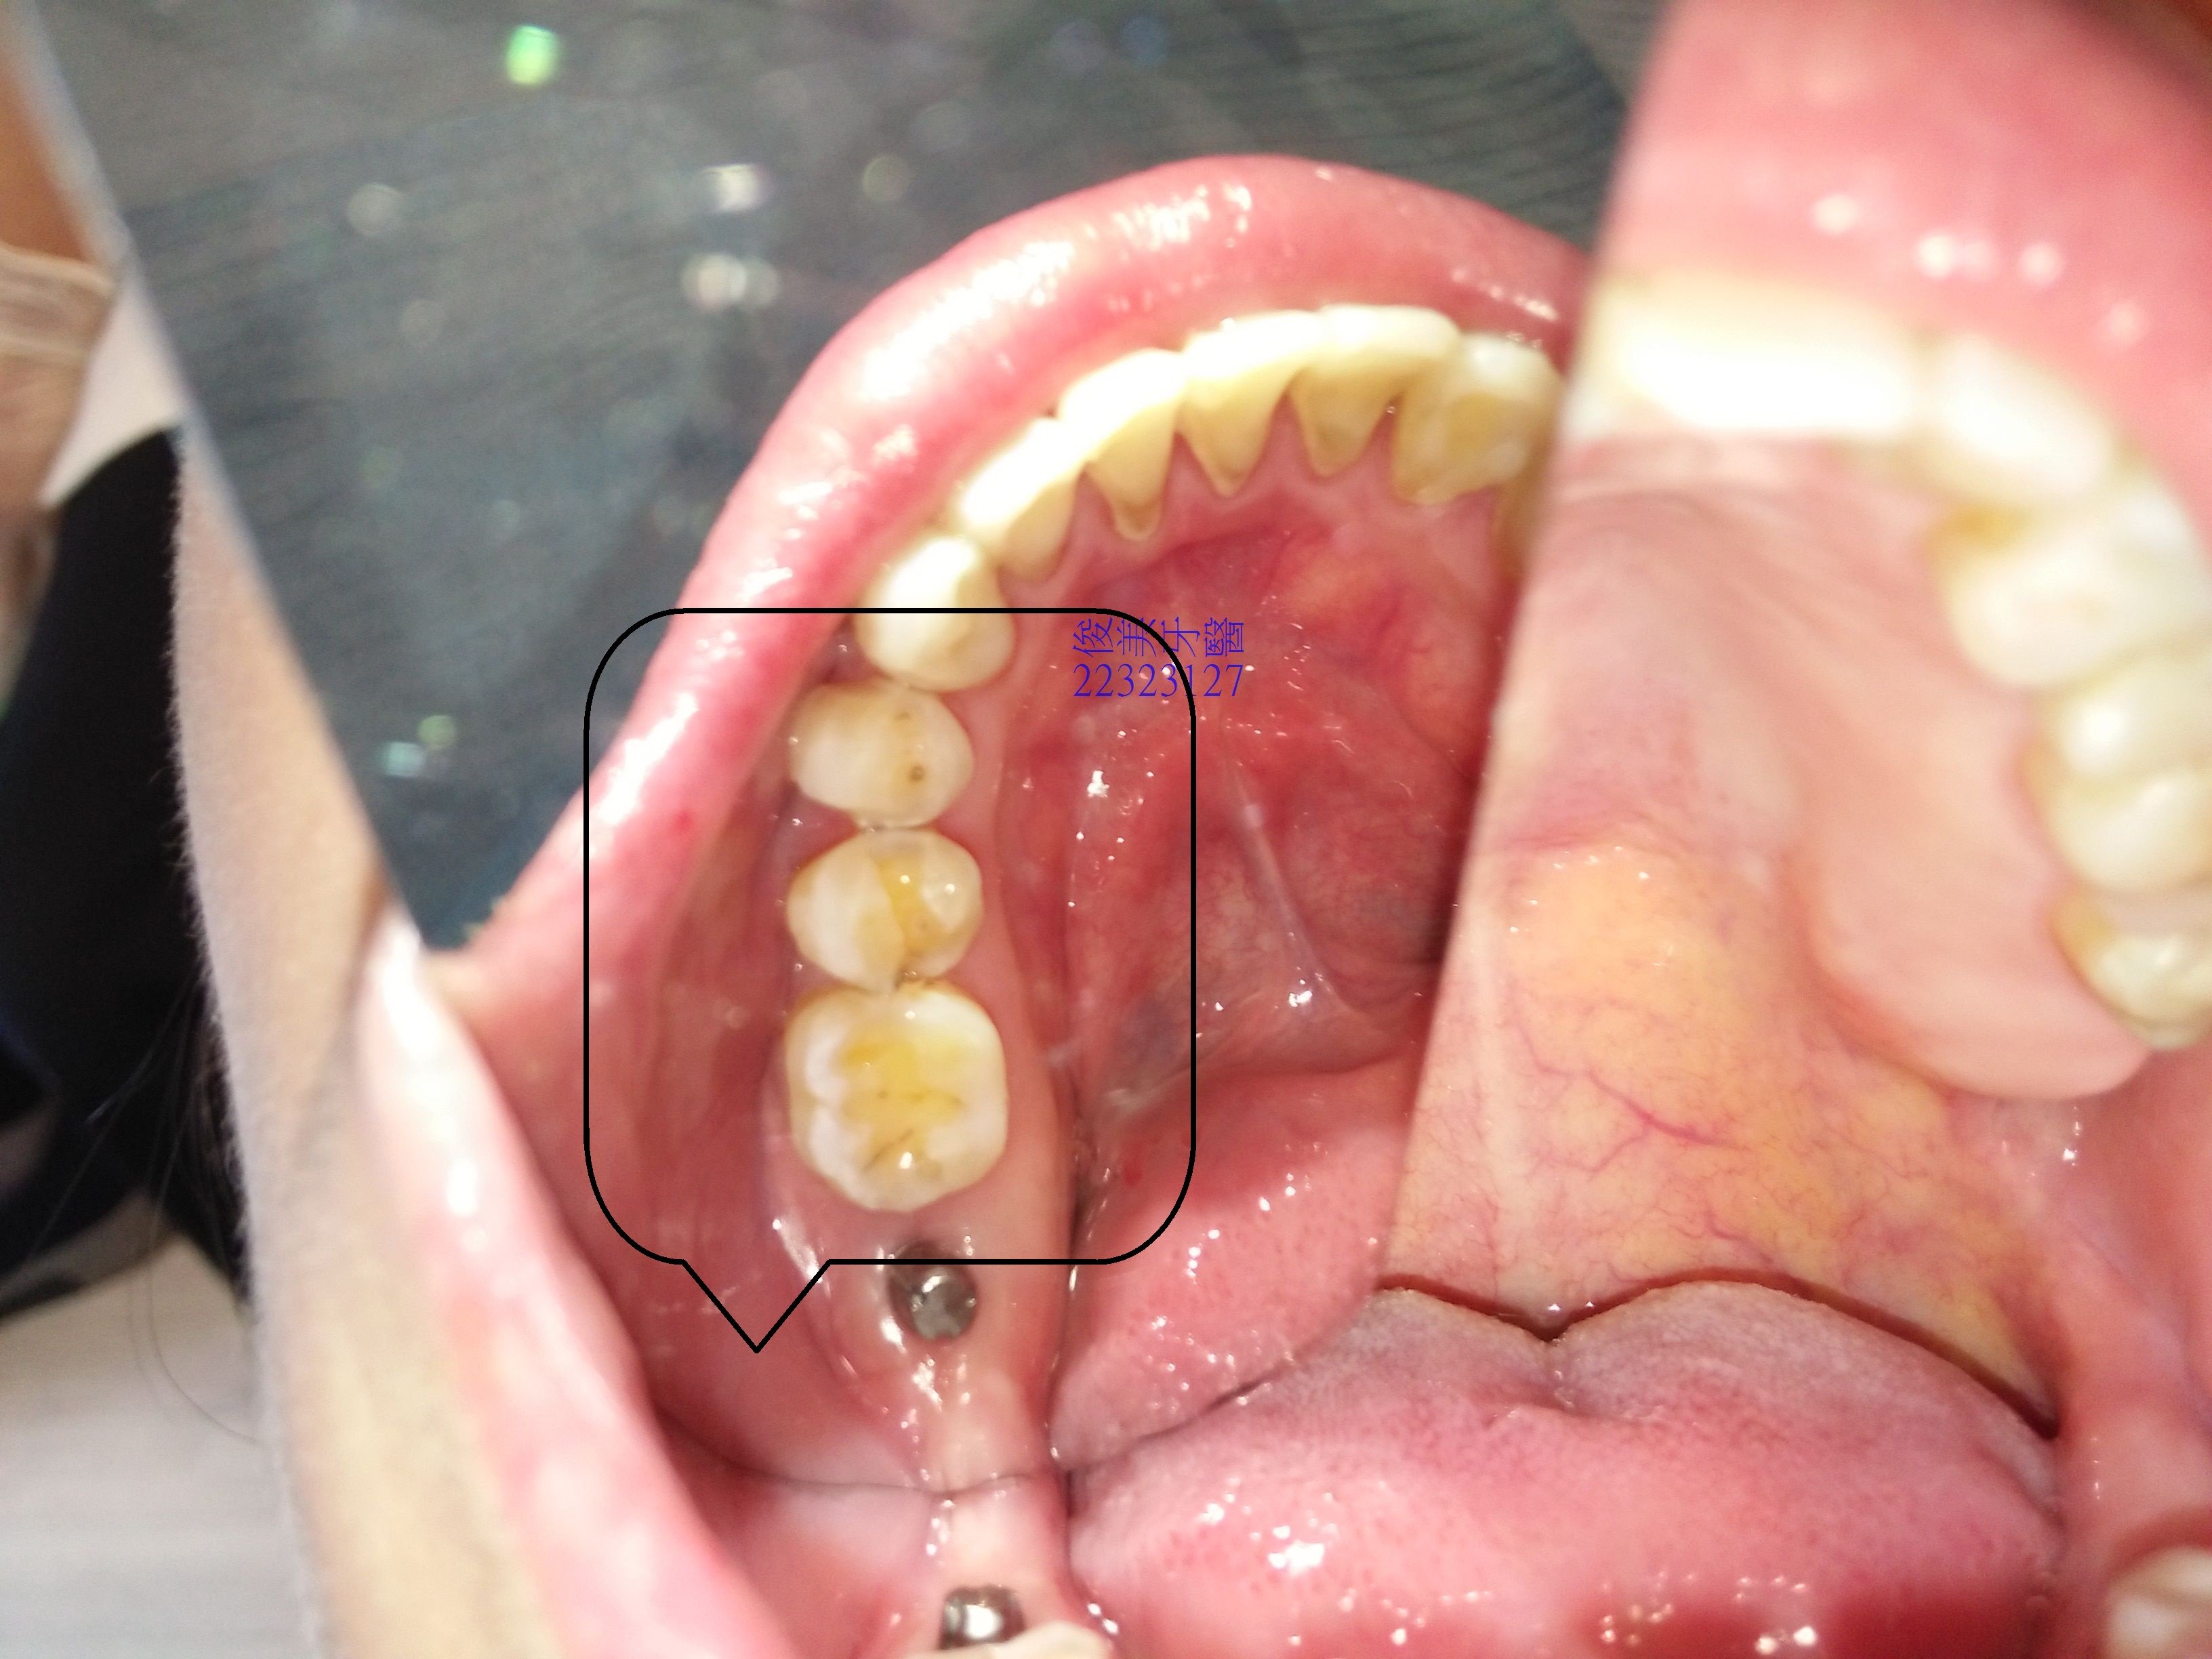

榫接式人工牙冠案例11

患者因多年前做過矯正,但當時因覺牙齒太暴,所以拔了牙做矯正,多年下來,牙齒都有過度磨損的現象,因此在醫師的評估後,決定採摩提斯牙冠來修復,避免破壞自已所剩無幾的琺瑯質,並先用臨時的來適應高度,在適應後即印模.....

不需修磨過多齒質,更加不用傷害牙齒寶貴的神經..

全瓷材質,達到最少破壞、最大修復效果,術後不敏感,可以使用牙線清潔。

至於缺牙採人工植牙修復,增加患者的支柱牙,分散牙齒全體的咬合力量,延長牙齒的壽命。